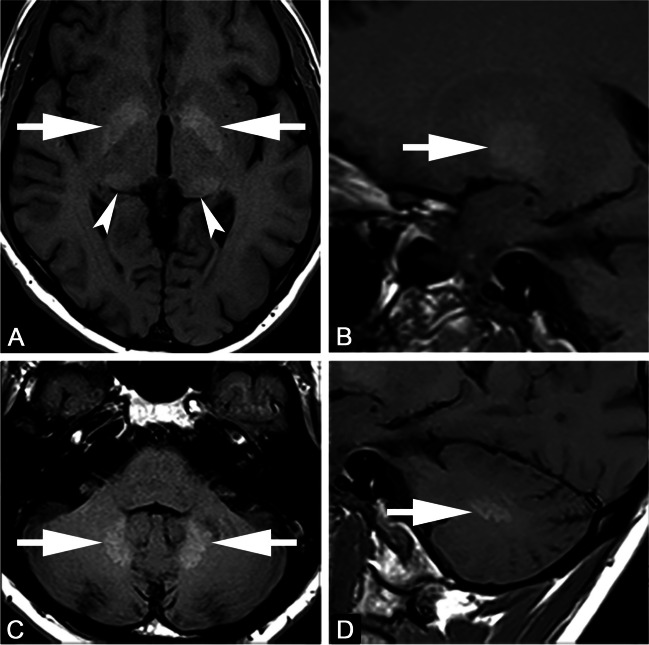

Fig. 1.

Axial (A, C) and sagittal (B, D) T1-weighted images. Forty-seven-year-old male with multiple sclerosis previously exposed to 14 intra-venous injections of gadodiamide. Globus pallidus and dentate nucleus hyperintensity on unenhanced T1-weighted images due to gadolinium deposition (arrows in A–D). Faint T1 hyperintensity of the pulvinar thalami is also seen (arrowheads in A)